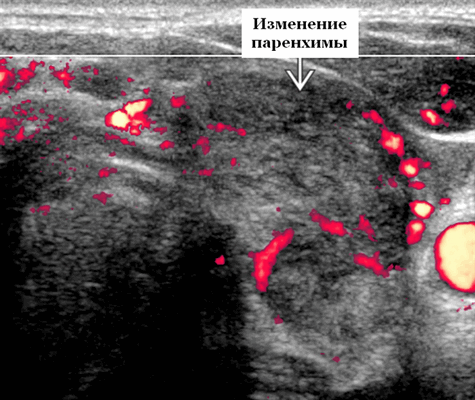

При проведении ультразвуковой диагностики выявляют плохо выраженный, гипоэхогенный, аваскулярный, субкапсулярный узел щитовидной железы у пациента с болезненным зобом и вирусным продромом. Диффузный зоб с пятнистым, гипоэхогенным, гетерогенным, гиповаскулярным / бессосудистым видом в подострой фазе. Расположение. Очаговый, субкапсулярный в острой фазе. Мультифокальный или диффузный; задействует всю железу, более одной доля в подострой фазе

- Острая фаза. Очаговая, плохо очерченная, гипоэхогенная узелковая область щитовидной железы; субкапсулярный по локации. Нормальная или гипоэхогенная, гетерогенная паренхима щитовидной железы. Болевая реакция при давлении датчиком на пораженную зону. По УЗИ с цветным допплером пораженные участки являются аваскулярными или гиповаскулярными. ± воспалительные узлы в центральном отделе и нижней внутренней яремной цепи

- Подострая фаза. Прогрессирование очагового поражения с диффузным увеличением одной доли или всей щитовидной железы. Пятнистые или слитые, плохо выраженные гипоэхогенные области. Остаточная чувствительность к давлению датчиком. По УЗИ с цветным допплером пораженные участки являются аваскулярными или гиповаскулярными. ± воспалительные узлы в области щитовидной железы